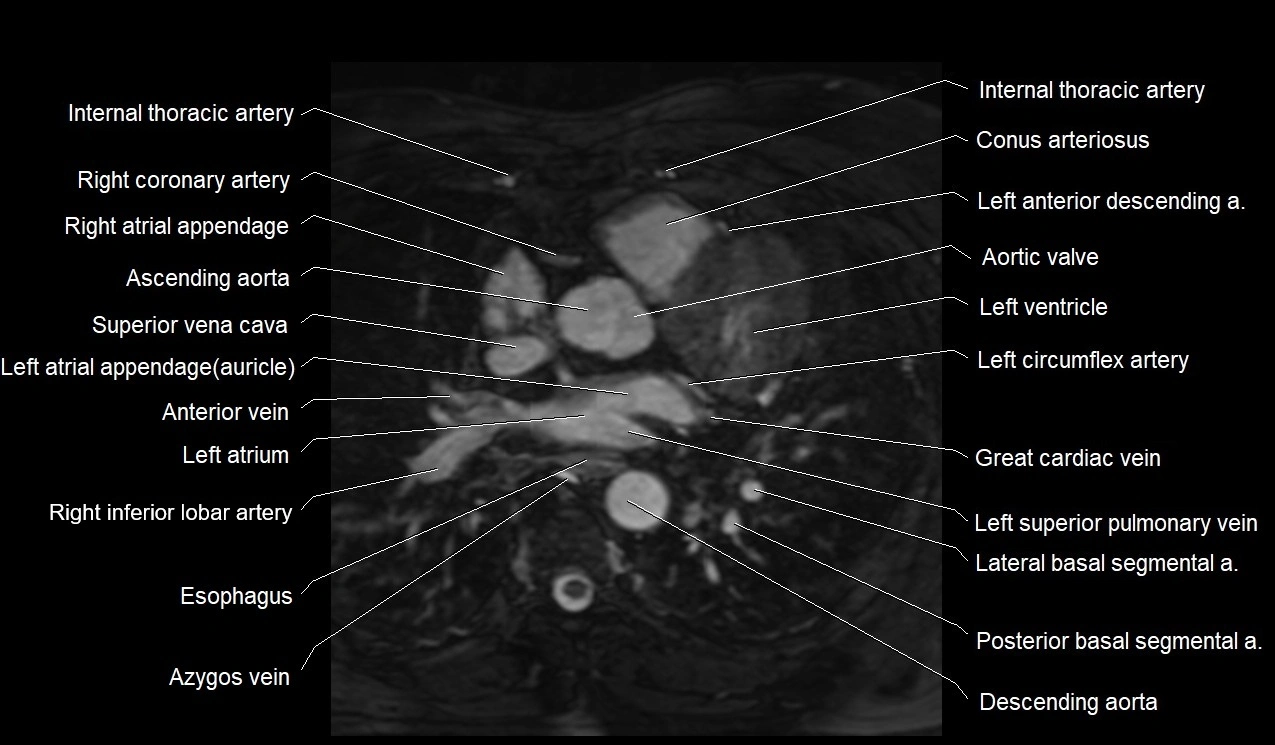

MRI image